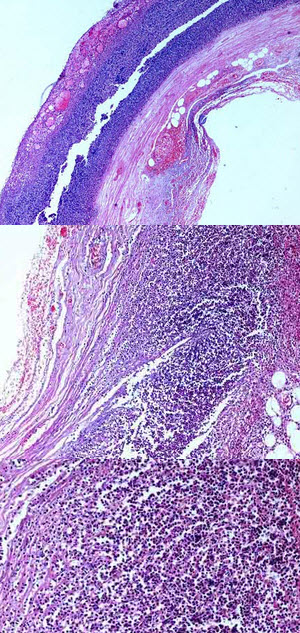

炎症病变中,主要有中性粒细胞和巨噬细胞两种吞噬细胞,其中巨噬细胞形态和名称可多种多样。

如图为肾结核结节镜下观,箭头所指细胞称之为()

3、单项选择题

患者,男,30岁。咳嗽、胸痛、低热1年。胸片示左肺上叶巨大阴影,边缘不清。手术切除病变肺叶送检。

该病变中的多核巨细胞是由下列哪种细胞演变而来的()

D.损伤血管基膜

镜检如图所示,最可能的诊断是什么()

B.仅由实质细胞增生形成